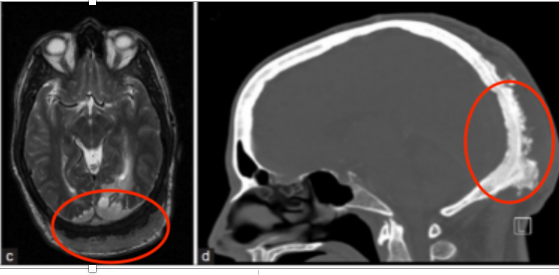

圖:軸向(a)和冠狀(b)對比增強(qiáng)的T1加權(quán)MRI證實(shí)腫瘤包裹著上矢狀竇的后部。觀察到后頭皮異常增厚。(c)軸向T2加權(quán)MRI序列顯示枕葉白質(zhì)異常高強(qiáng)度,與實(shí)質(zhì)性腫瘤浸潤引起的血管性水腫一致。(d)增強(qiáng)CT掃描,顯示枕骨由于腫瘤浸潤而變厚的骨質(zhì)肥大。